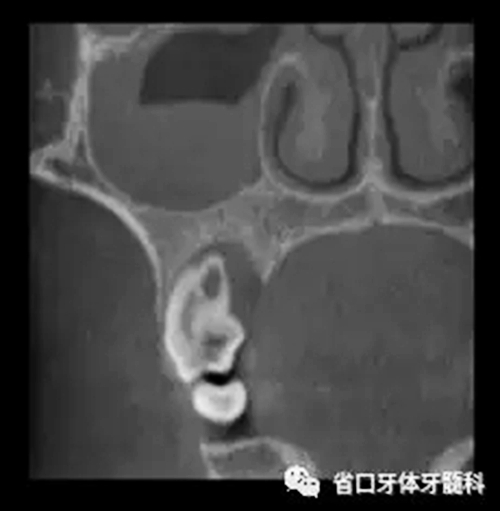

圖3 CBCT(2016-11-13):15由髓腔至根管內(nèi)見團塊阻射影像,阻射影中央為透射影,根尖1/3處見根管膨大,腭側(cè)牙槽骨破壞,根尖周低密度影范圍大,上頜竇黏膜增厚。